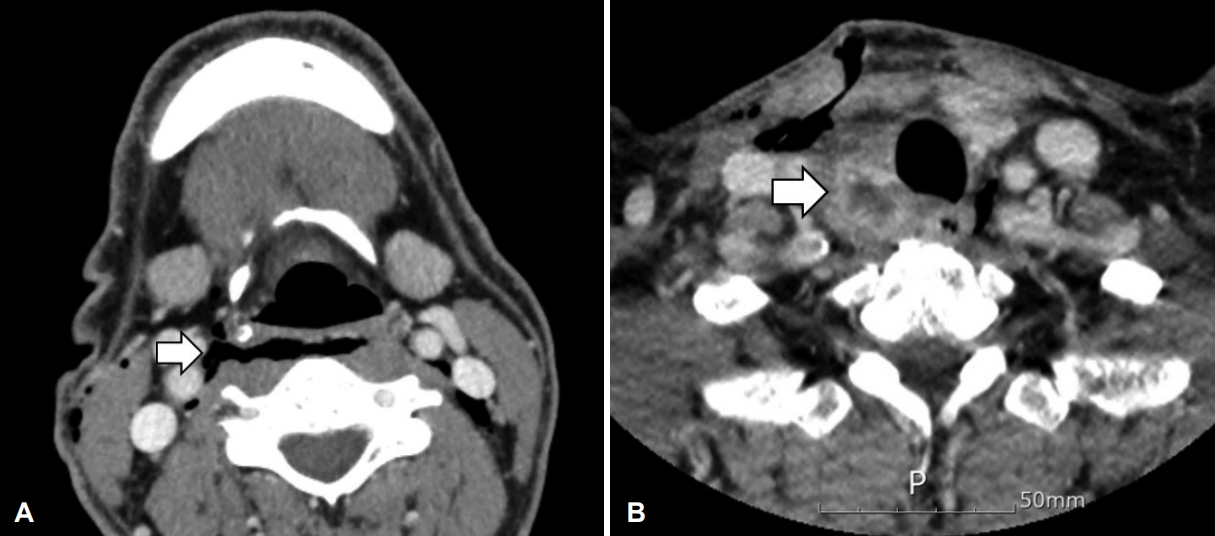

병리조직 검사 결과는 급성 화농성 감염 소견을 동반한 지방 조직이 보였고, 결핵 중합효소 반응 검사에서 음성이었다. 술 후 3일째에 시행한 전산화단층촬영 검사상 기관 주위에 종물의 염증성 소견은 호전이 없었고 다른 후인두 병변들은 호전되었다(Fig. 3). 인후통, 발열 증상은 호전되었으며, 혈액 검사상 백혈구 4.71(×103/μL, 3~9.3), 분엽 호중구 44.3(%,40~70), 적혈구침강속도 58(mm/hr, 0~30), C-반응단백 0.56(mg/dL, 0~0.5)으로 염증 수치의 호전 양상을 보였다. 다학제적 회의 후 기관 낭종의 감염으로 인한 후인두 농양으로 진단되었다. 환자는 특별한 합병증 없이 수술 후 10일 뒤 퇴원하였다. 2개월 뒤 외래에서 추적 검사로 시행한 전산화단층촬영상 우측 기관 주위 농양강은 대부분 줄어들었으며, 농양이 있었던 기관의 우측 후방부에서 낭종이 발견되었다(Fig. 4). 기관에서 낭종 확인을 위해 기관내시경을 시행하였으나 연결 부위나 다른 특이 소견은 보이지 않았다. 기관 낭종의 염증 소견이 호전되었고, 염증이 동반되는 경우가 드물기 때문에 향후 재발 시 근치적 수술을 고려하기로 하였다. 수술 후 1년간 외래 경과 관찰 중 염증의 재발 소견은 없고, 영상 검사에서 낭종의 변화 소견은 없었다.